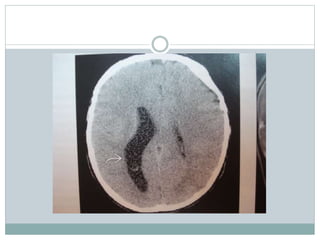

TAC hemorragia cerebral